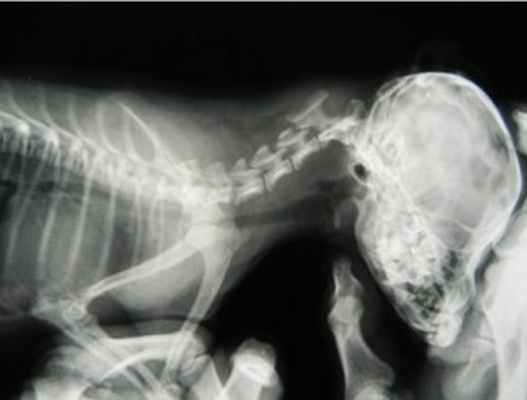

При проведении рентгенологического исследования шейного отдела позвоночника сбоку, у животных с атлантоаксиальной нестабильностью обычно выявляются отклонения в расположении позвонков (изменение расстояния между ними и параллельности остистых отростков). В сомнительных случаях, врач ветеринарной клиники может использовать для диагностики стрессовую радиографию, когда у животного проводится принудительное сгибание подбородка в сторону грудной клетки, данный вид исследования должен проводиться с большими предосторожностями во избежание катастрофических результатов сдавления (компрессии) спинного мозга.

Рентгеновский снимок позволяет достаточно четко визуализировать область АА сустава, преимущественно у карликовых пород собак, ввиду очень незначительной толщины позвонков (средняя толщина дорсальной дужки атланта в период с 1-3 месяцев составляет 1- 1.2 мм. (McCarthy R.J., Lewis D.D., 1995)). Также по ренгеновскому снимку можно оценить увеличение расстояния между позвонками С1 и С2.

Снимок, рекомендуется проводить без общей анестезии, так как расслабление и снятие болевого синдрома (если таковой имеется) усугубит повреждение спинного мозга, что может вследствие восходящего отека привести к параличу дыхательного центра и летальному исходу.

Однако нельзя никаким образом судить о компрессии спинного мозга на основании рентгеновского снимка. (Сотников В.В.,2010.) Для этого необходимо выполнить КТ или МРТ.